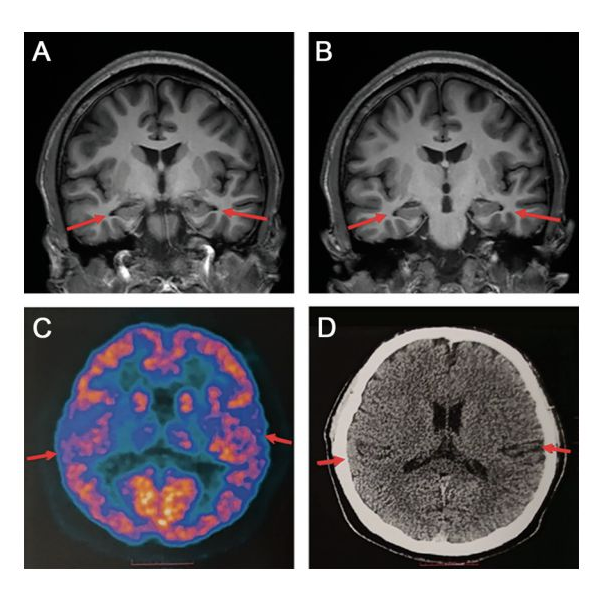

AD病理示意图